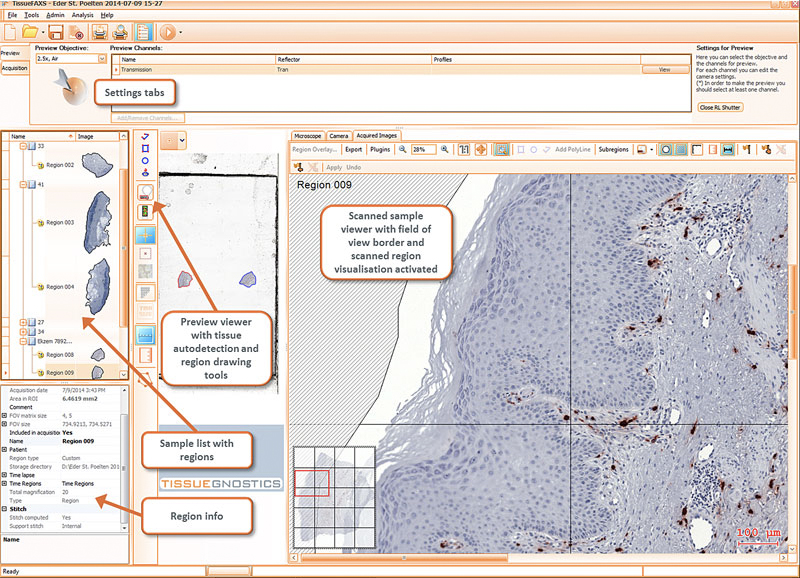

TissueFAXS正置系统和TissueFAXS i倒置系统均搭载多模式扫描软件,采用全自动全景扫描模式,适配各种类型样本的图像获取,例如标准组织切片,超大组织切片,细胞爬片,细胞培养瓶,微孔板等。在扫描过程中,可选智能/手动获取全样本聚焦平面,支持区域实时重新获取,以及扫描文件数据库管理等功能,可以满足Z-stack扫描、延伸聚焦、超大尺寸图像无缝拼接、明场荧光阴影矫正等高级图像质量扫描需求。

TissueFAXS实现了良好的软硬件整合,灵活的远程操控手段,简单快捷的扫描操作以及可靠的无人值守自动扫描及分析流程。

切片预读取